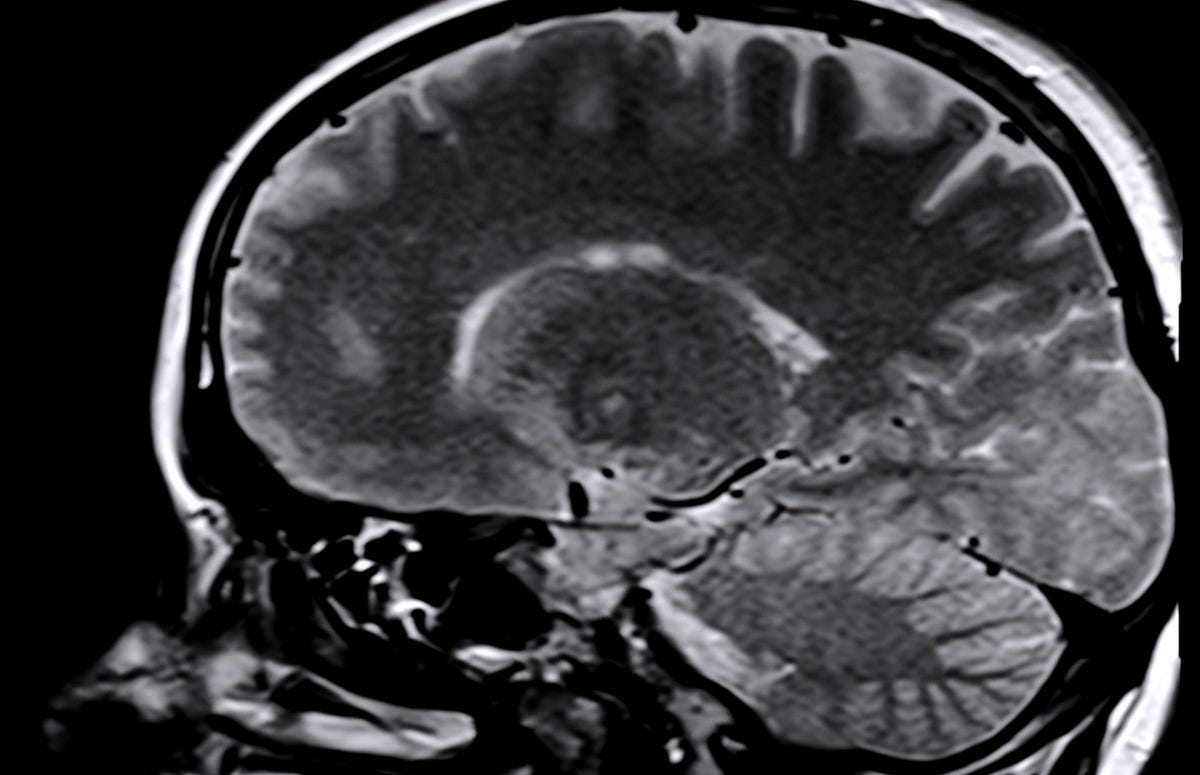

Rare Brain Cells Link Stress, Blood Flow & Dementia Risk

Penn State researchers found that a rare neuron type—type-one nNOS—helps regulate blood flow and brain-wide signaling. These cells die easily under chronic stress, possibly linking stress directly to cognitive decline.

A&P teaching tip: Add this to lessons on neurovascular coupling or the impact of psychological stress on brain health. It’s a great example of how tiny populations of cells can have outsized effects.

Read more→ AandP.info/8f09c6